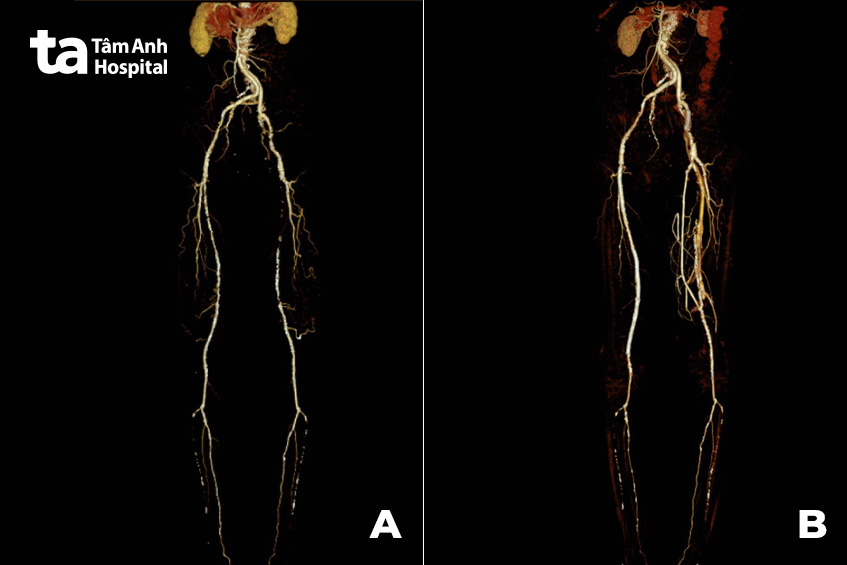

Bác sĩ Dũng cho hay bệnh nhân tái khám tại các thời điểm sau đó, được tiến hành các thăm dò đánh giá lại cho thấy chỉ số tưới máu hai chân (ABI) đã trở về giá trị bình thường. Phim chụp MSCT mạch máu xác định chi dưới được tưới máu đầy đủ, các vị trí bắc cầu nối cũng như vị trí đặt stent cho dòng chảy trơn tru.